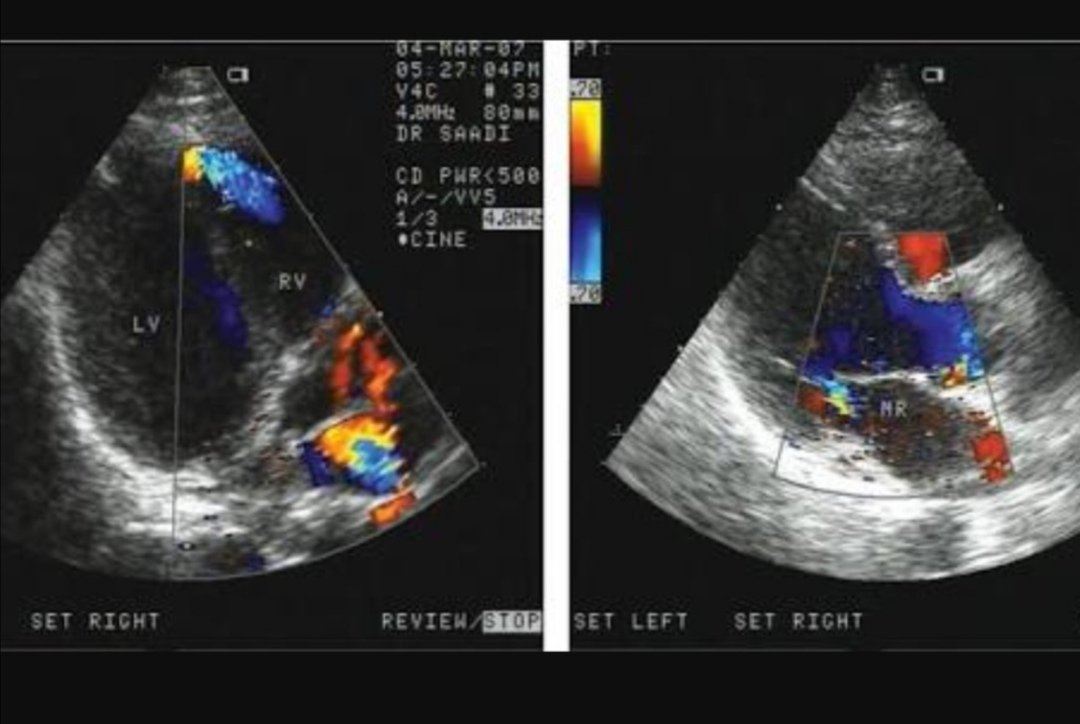

خلال فترة التنويم يتم عمل الأشعة التلفزيونية الدوبلر في :

👈 اليوم الأول بعد العملية

👈اليوم الأخير من التنويم قبل الخروج وذلك لفحص الأوردة والشرايين للجزء المتبقي من الكبد